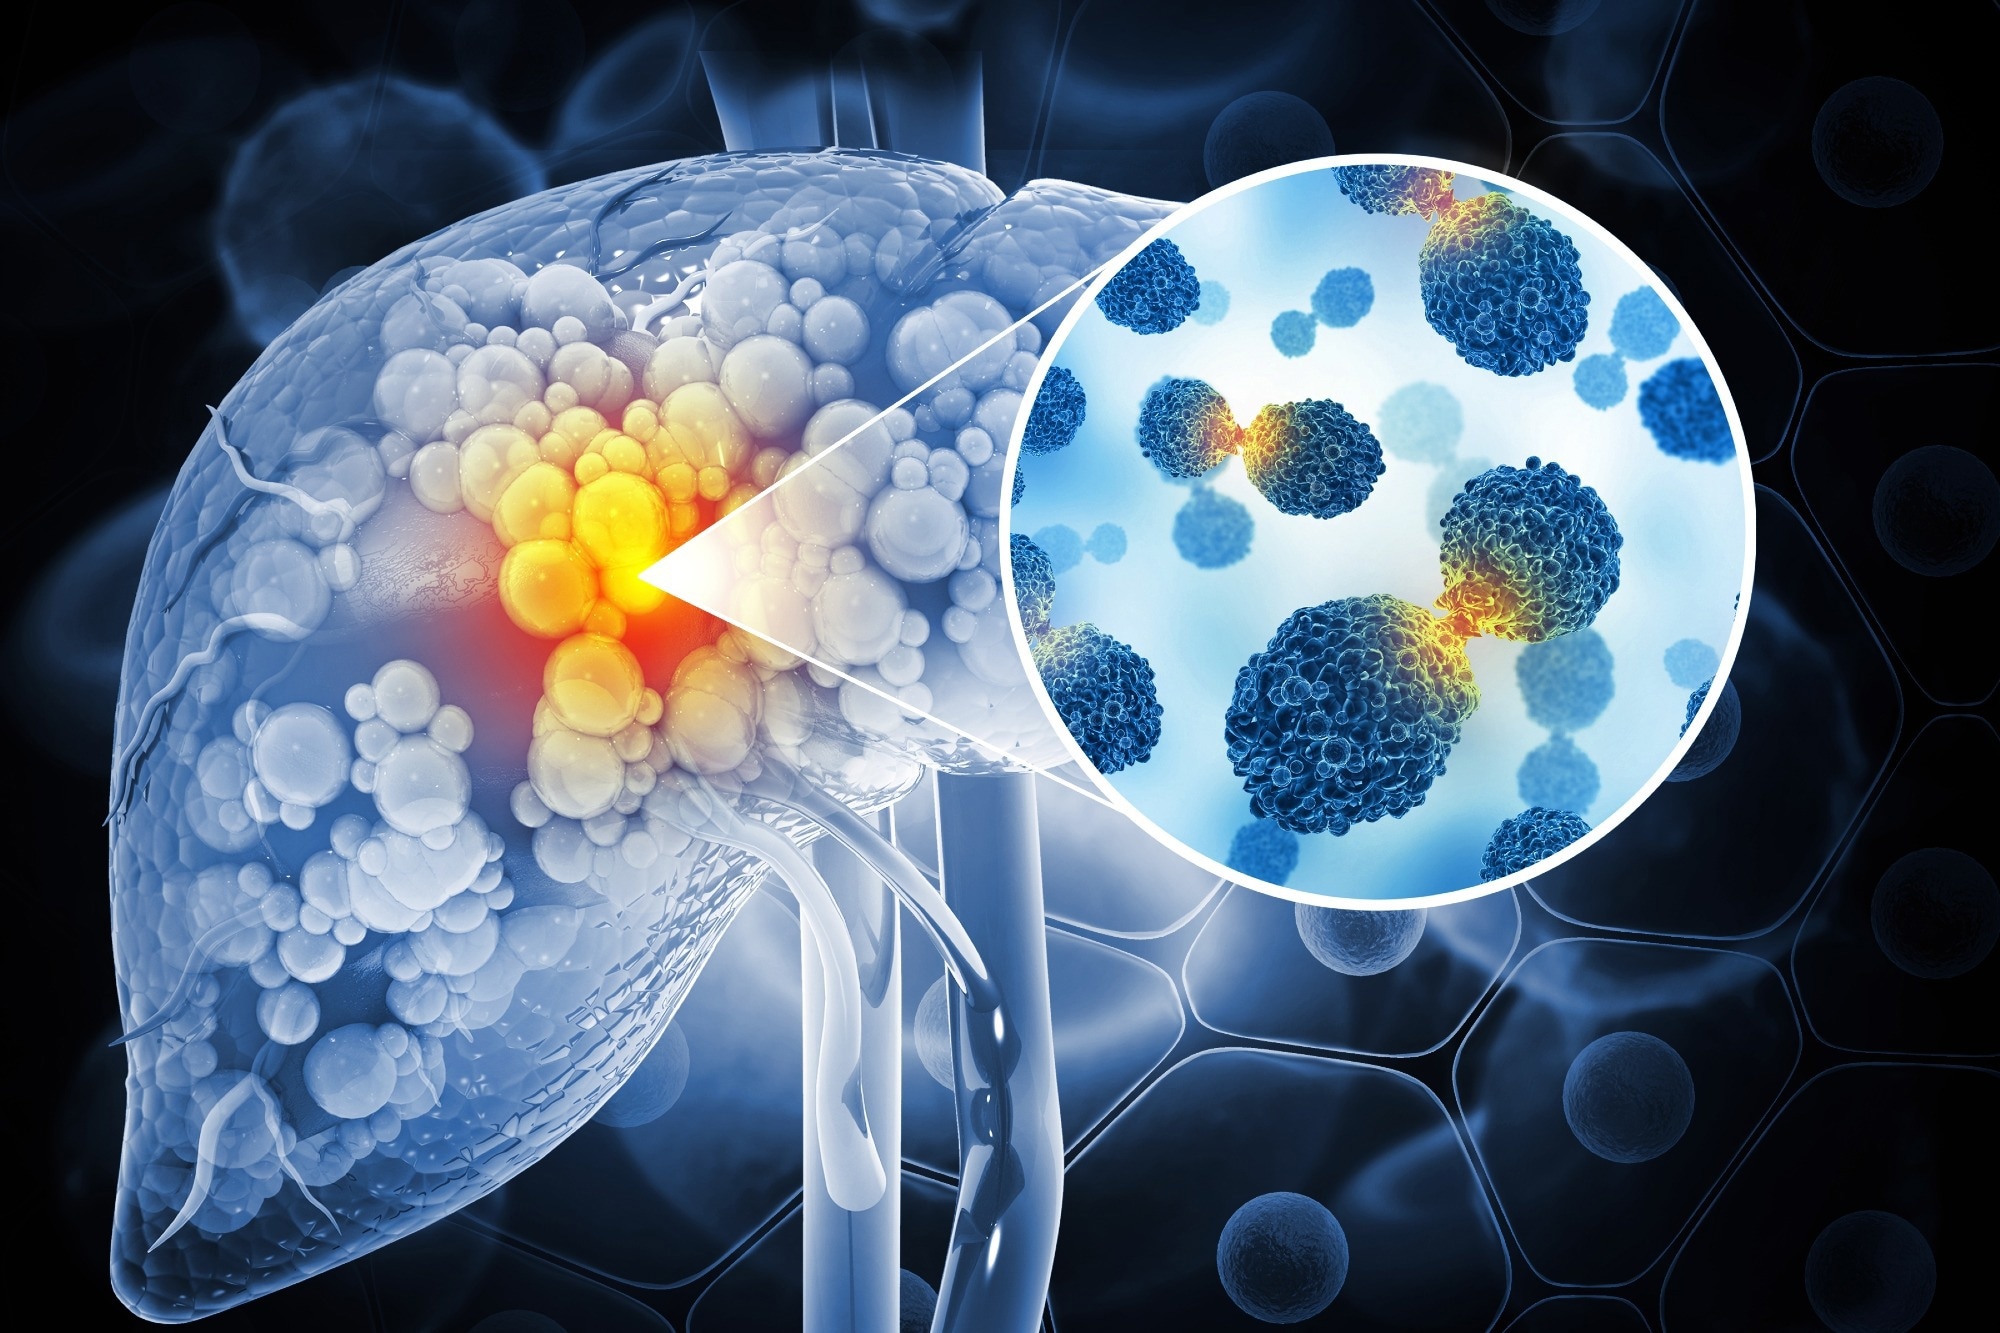

A new ultrasound-guided nanotherapy wipes out liver tumors while training the immune system to keep them from coming back.

Image Credit: crystal light/Shutterstock.com

The study, published in Nano Today, introduces a biodegradable nanoparticle system that combines sonodynamic therapy and cell death induction (ferroptosis) to treat hepatocellular carcinoma, the most common type of liver cancer.

Hepatocellular carcinoma is one of the most challenging types of liver cancer to treat due to poor immune responsiveness and high recurrence.